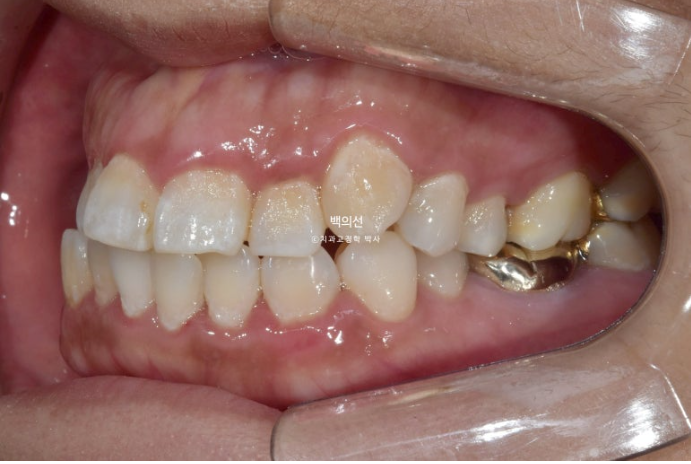

턱의 비대칭도 있어 앞니 치아중심선이 약 2mm 어긋나 있으며 아래턱이 돌아간 우측으로 송곳니와 어금니가 반대 교합입니다.

공간이 좁아 덧니도 있고

앞니 배열도 개선이 필요합니다.

덧니도 있고 돌출도 심하니 작은어금니 4개 발치교정이 필요한 상황입니다.

그런데 파란 화살표 부분에 큰어금니가 하나 없습니다.

오래 전 큰어금니가 빠진 부분을 브릿지로 치료해 놓은 상태입니다.

치료의 편의성을 위해서는 작은어금니 4개 발치가 필요하나 브릿지 자체가 오래되기도 해서 파란 화살표쪽 분악은 추가적인 소구치 발치 없이 브릿지를 잘라내어 큰어금니 빈공간에 이용하기로 합니다.